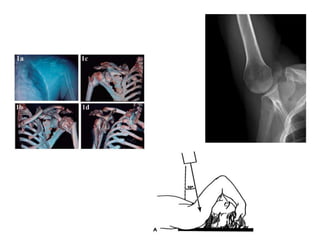

Fracturas de porción superior del húmero:

Son necesarias dos radiografías: anteroposterior y axial. También

es conveniente realizar la proyección lateral de hombro.

Fracturas de escápula:

Antero-posterior y lateral para cuerpo y acromion;

proyección Stryker para practuras de la apófisis

coracoides.

TAC con reconstrucción 3D en plano transversal.